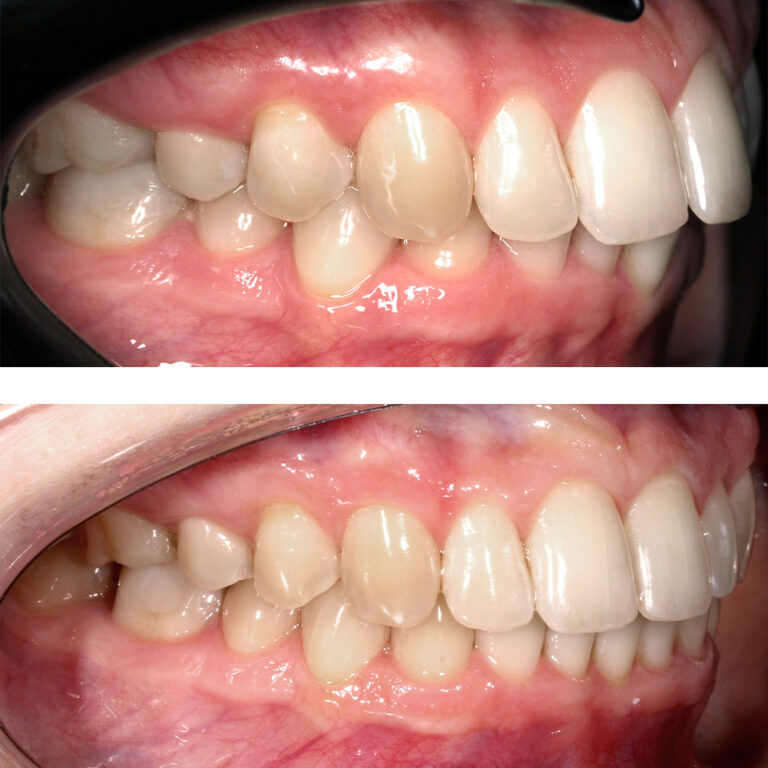

Кейс 13

Булгач (Мочалова) Галина Игоревна

Количество кап ВЧ 19

Количество кап НЧ 24

ДО

ПОСЛЕ